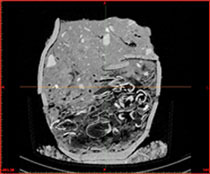

Uusi, vähitellen arkeologienkin käyttöön tullut kuvantamismenetelmä on tietokonetomografia (TT, engl. Computed Tomography, CT). Tietokonetomografialaitteet kehittyvät nykyään nopeasti. Vanhoiksi jääneet laitteet eivät enää kelpaa lääketieteelle, mutta ovat tervetullut lisä arkeologiseen tutkimukseen. Tietokonetomografia on röntgenmenetelmä, jossa kohteesta otetaan useasta eri suunnasta tähdätyillä röntgensäteillä satoja projektiokuvia, joista muodostetaan ns. leike, eli tietyn levyinen poikkileikkaus kohteesta. Kohteesta voidaan kuvankäsittelyn avulla muodostaa kolmiulotteinen kuva, toisin kuin perinteisessä röntgenkuvaamisessa. TT-kuvaus myös näyttää metalliesineiden lisäksi kaikki haudassa olevat muut materiaalit, kuten luut ja tekstiilit. Kohteesta saatu tarkka, kolmiulotteinen kuva voi vastata moniin eri kysymyksiin, kuin vain siihen miltä kohde kokonaisuudessaan näyttää.

Varsinaisessa ruumishautatutkimuksessa tietokonetomografiaa on käytetty taidokkaasti Saksan Lauchheimin varhaiskeskiaikaisen kalmiston kaivauksissa. Kaivaukset ovat suoritettu vuosien 1986 ja 2005 välillä ja alueelta on löydetty n. 1300 hautaa. Kipsattuja hautoja on jälkeenpäin tutkittu tietokonetomografian avulla eräänlaisena pilottiprojektina Freiburgin yliopiston ja Saksan ”Museoviraston” DFG:n yhteistyönä. Pilottiprojektin tavoitteena on kehittää alan metodeja ja tutkia tietokonetomografian hyötyjä ja etuja arkeologisessa tutkimuksessa. Tietokonetomografian hyödyiksi luetellaan sen kyky näyttää kaikki haudan materiaalit, sekä mahdollisuus kolmiulotteisen mallin luomiseen, mutta myös sen tarkkuus tekstiilien kuvaamisessa. Toisiinsa, tai muihin esineisiin takertuneita tekstiilejä voi läpileikkauskuvien avulla tarkastella kerros kerrokselta. Lisäksi 3D-mallin avulla haudassa olevia hajonneita esineitä voi rekonstruoida virtuaalisesti, ennen kuin niitä on edes kaivettu esiin. Tietokonetomografialla on myös pystytty rekonstruoimaan roomalaisesta haudasta löytynyttä pirstaleista lasiaineistoa. TT-kuvista kyettiin päättelemään lasiastioiden sijainti, lukumäärä ja muoto. Myös itse haudan rekonstruoiminen kaikkine esineineen tehtiin tietokonetomografian avulla. Haudan sisällön tietäminen etukäteen antaa arkeologille enemmän mahdollisuuksia miettiä kohteen kaivamistapaa ja konservaattorille mahdollisuuden varautua tarvittaviin konservointimenetelmiin.